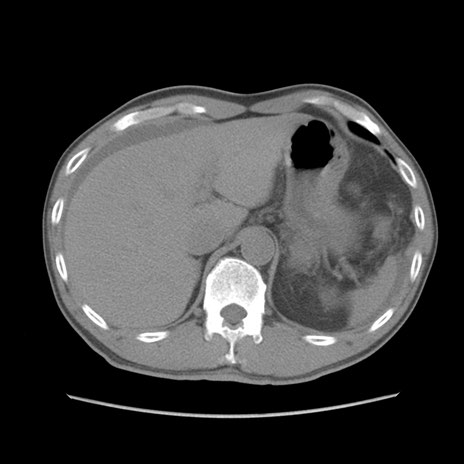

症例56 CT(横断像)

脂肪ウインドウ